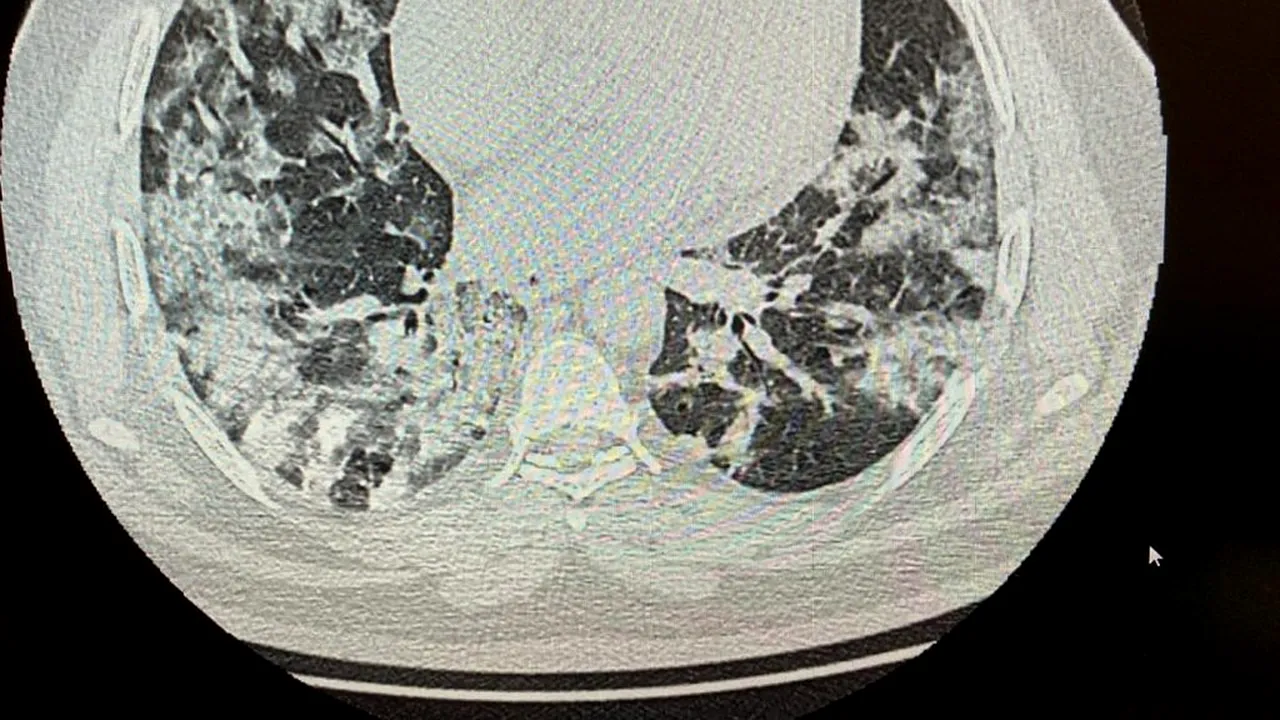

Medicul Adina Cojocaru a publicat o imagine cu un CT făcut unui pacient de 37 de ani, cu pneumonie din cauza noului coronavirus. Potrivit medicului, pacientul are 37 de ani și necesită internare la ATI, asta după ce a dus boala pe picioare.

„Un caz de azi noapte. Pacient in vârstă de 37 ani, se prezintă la camera de gardă Floreasca pentru sdr subocluziv intestinal și subfebrilitate. CT-ul lui arată pneumonie interstițiala. Are 65 saturatie in oxigen. Pentru el definiția de caz a Institutului de Sănătate Publică nu mai face doi bani. Și sunt multe asemenea cazuri, cele mai multe atipice, mulți au doar somnolență, astenie, cefalee.

„Imaginea CT e atât de sugestivă, saturația în oxigen nu mai spun”

„Imaginea CT e atât de sugestivă, saturația în oxigen nu mai spun, pacientul va pleca la lași sau în Medgidia pe locuri eliberate în ATI. Acolo îl așteaptă Dumnezeu cu mila lui. În Bucuresti nu mai sunt locuri libere. Deci cum facem domnule și doamnă doctor Bittman și Chiriac, intră la numărătoare sau nu?”, a mai scris Adina Cojocaru.